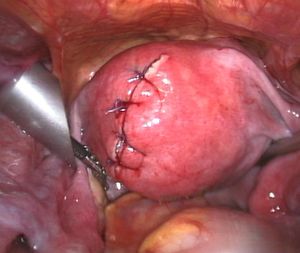

| Uterine fibroids as seen during laparoscopic surgery | |

- A laparoscopic myomectomy is done through a small incision near the navel. The physician uses a laparoscope and surgical instruments to remove the fibroids. Studies have suggested that laparoscopic myomectomy leads to lower morbidity rates and faster recovery than does laparotomic myomectomy.[61]